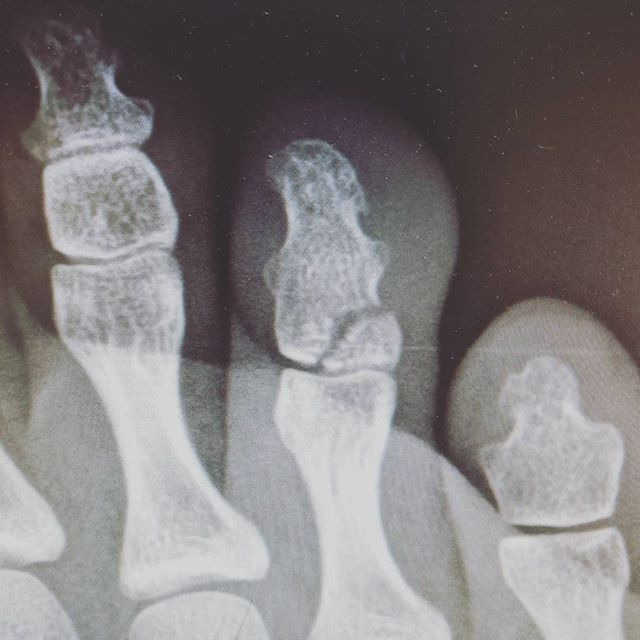

골절 유형

- 단순 골절: 뼈가 한 번 금이 가거나 깨진 정도로, 비교적 뼈 조각이 많이 어긋나지 않은 경우입니다.

- 복합 골절: 뼈가 여러 조각으로 나뉘거나, 뼈가 제 위치에서 크게 어긋난 경우입니다.

- 압박 골절: 압력에 의해 납작하게 뭉개지듯 부러진 형태이며, 골절 부위가 복합적으로 손상되기 쉽습니다.